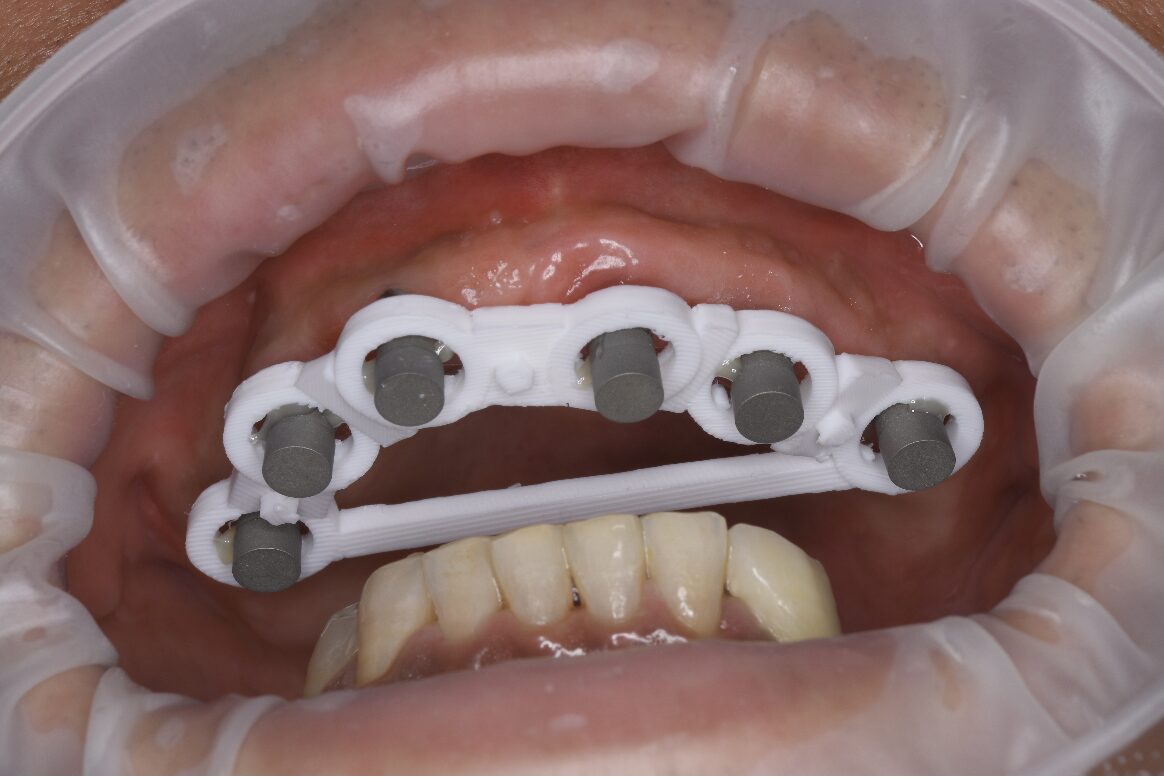

ステップ2:インプラント埋入手術

抜歯した部分の歯肉の傷口が十分に治癒したことを確認してから、CTデータに基づいた精密なシミュレーションのもと、上顎に6本のインプラントを埋入する手術を行いました。

ステップ2画像

【当院の強み:高精度のデジタル技術と学会発表】

今回の治療では、インプラントの埋入位置のシミュレーションから、最終的な歯の設計・製作に至るまで、デジタル機器(口腔内スキャナーやCAD/CAMシステムなど)を駆使して行いました。 これにより、精度の高い治療と、機能的かつ審美的な仕上がりを両立が期待できます。

また、本症例は他院で断られた難症例をデジタル技術で克服した有意義なケースであったため、症例報告として学会発表させていただきました。 その結果、光栄なことに「日本臨床歯科CADCAM学会」において最優秀アワードを受賞いたしました。